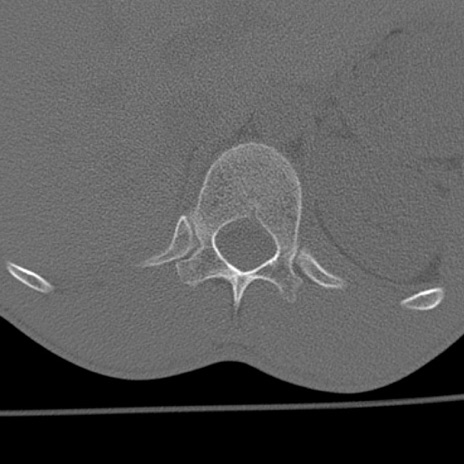

症例3 腰椎CT(横断像)

腰椎CT